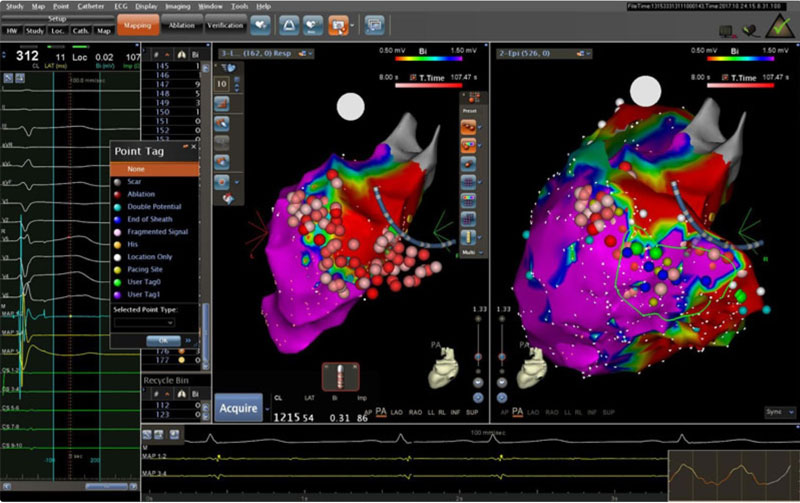

Впервые в России выполнена эпикардиальная абляция при синдроме Бругада

В Пироговском Центре создана соответствующая мировым требованиям эпилептологическая служба:

- Мультидисциплинарная команда (врачи разных специальностей, инженеры, лингвисты, математики и аналитики, специалисты IT)

- Высокотехнологичная нейрохирургическая служба

- Современная нейрофизиологическая лаборатория

- Передовая анестезиологическая служба

- Современная нейровизуализация (МРТ, ОФЭКТ, SISCOM)

Внедрен современный протокол диагностики эпилептогенных очагов головного мозга — протокол SISCOM (Subtraction Ictal SPECT Co-Registered to MRI)

Внедрение хирургического лечения эпилепсии с роботизированным инвазивным нейромониторингом